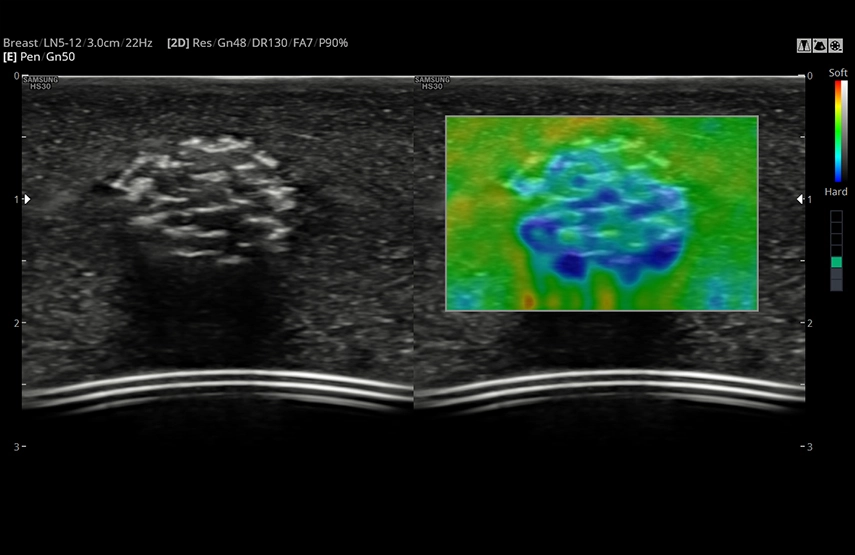

- Elastoscan – компрессионная эластография (качественная оценка);

- ElastoScan - диагностическая ультразвуковая технология визуализации эластичности тканей ElastoScan помогает определить в тканях плотные образования, предоставляя информацию о жесткости в виде цветовой карты.

- Линейный датчик LN5-12, 5-12 МГц, апертура 38 мм;

ElastoScan (Phantom)